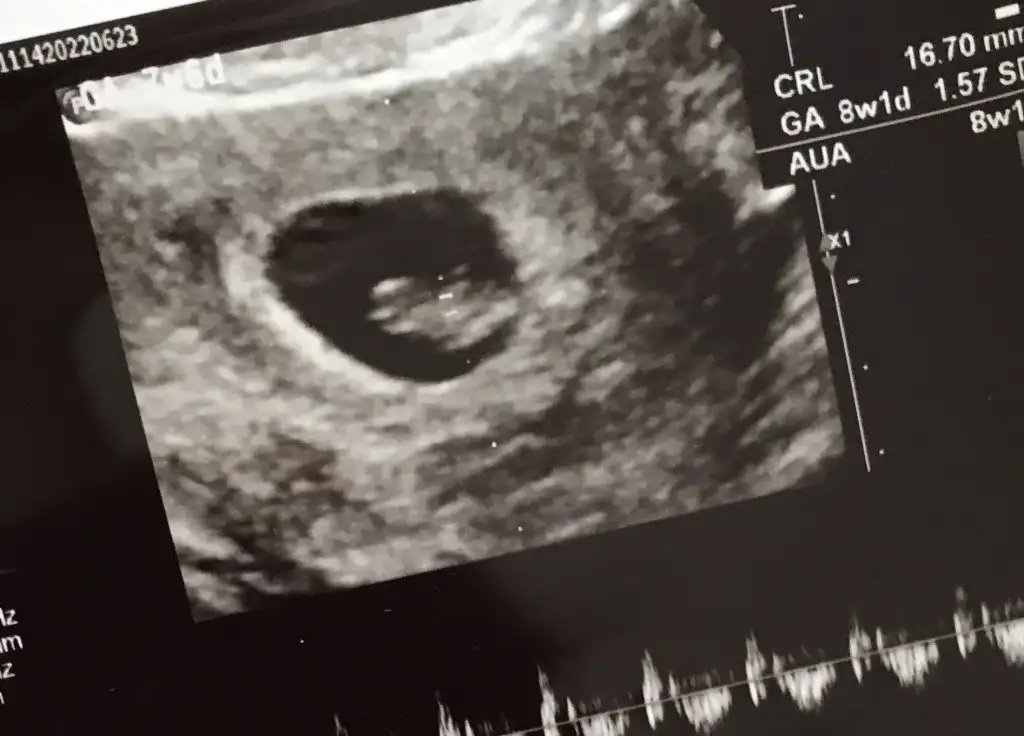

Merhaba 7 buçuk haftalık tahmin ederseniz sevinirim☺️

• IMG-20220628-WA0005.webp

IMG-20220628-WA0005.webp

21,7 KB · Görüntüleme: 67